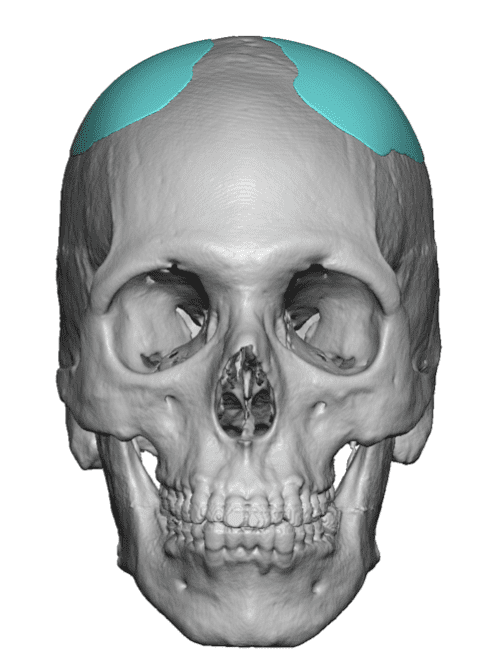

Severe narrowing skull deformity from prior sagittal craniosynostosis repair as an adult.

Complete replacement of entire skull by a custom implant with temporal fat injections.